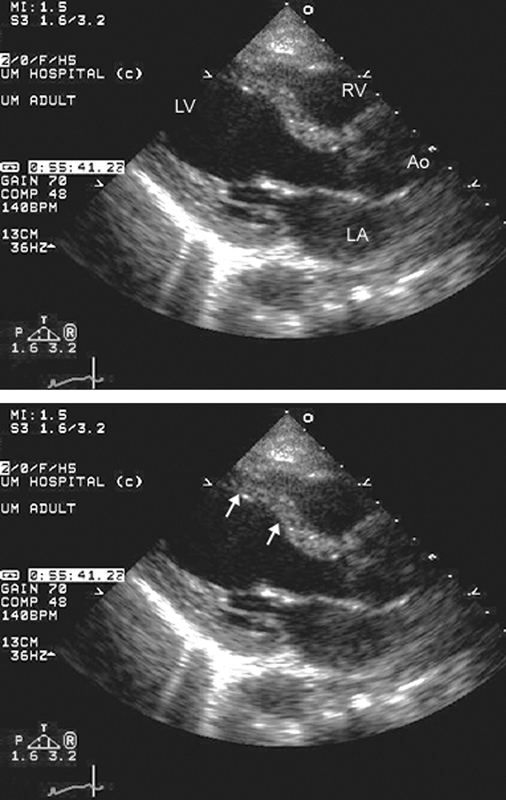

فحوصات تشخيصية لبعض امراض القلب والشرايين التاجية